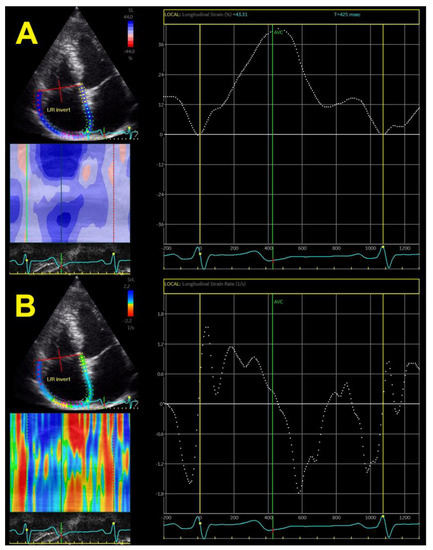

RA phasic function, determined by different segments of the longitudinal strain curve, showed impairment that correlated with systolic BP. Strain-derived RA phasic function is faster, easier, and more reliable and reproducible than volume-derived RA phasic function and, therefore, might be easily used in clinical practice and not only for research purposes (Figure 4A). RA strain rates provide additional information about the RA phasic function (Figure 4B).

Figure 4.

Two-dimensional right atrial strain (A) and strain rates (B).